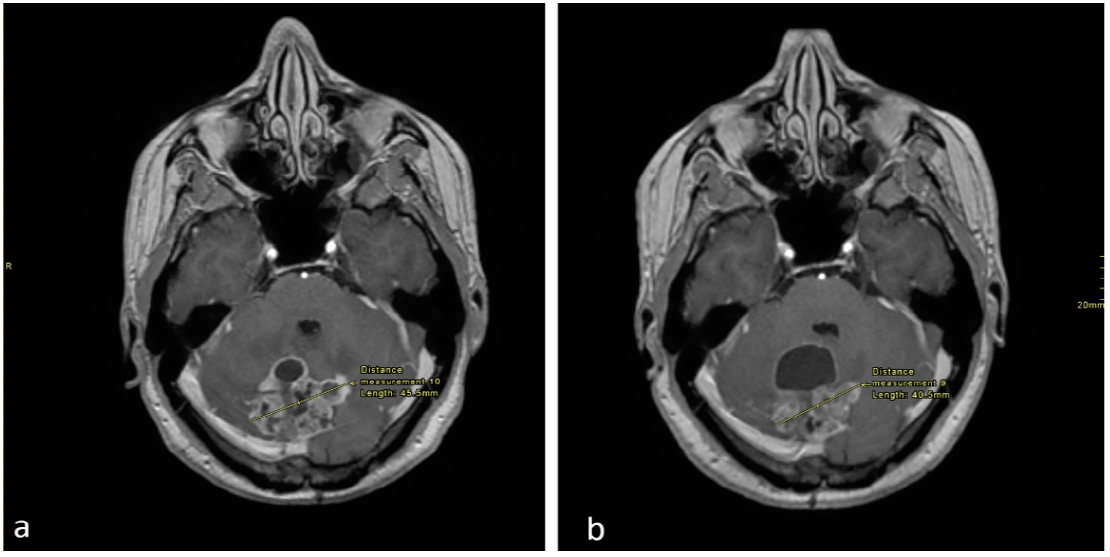

Follow-up MRIs after 6 and 9 months of treatment in December 2017 and March 2018 revealed reductions in the solid components of both the cerebellar and pineal masses, despite an increase in the cystic component and persistent hydrocephalus (Figure 1 and Figure 2). Since the patient was asymptomatic, dexamethasone was discontinued at that point.

Figure 2. Axial enhanced T1 weighted images of the brain at the level of the pineal region. (a) Imaging performed in September 2017 and (b) in December 2017. There is an interval decrease in the size of the tumor, as shown.